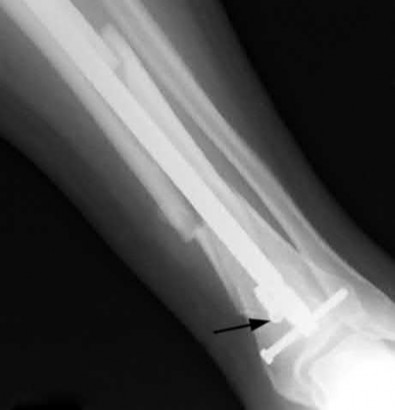

A 25-year-old female is involved in a motor vehicle collision. She presents with the isolated injury seen in Figures A through D. Her leg is swollen but her skin is intact. She has no clinical signs of compartment syndrome. Which of the following treatment options will allow for maintenance of fracture alignment and minimize the risk of soft tissue complications?

The patient presents with a closed distal third metaphyseal-diaphyseal distal tibia fracture with simple intra-articular extension. Immediate intramedullary nailing along with percutaneous fixation of the articular component provides appropriate restoration of length, rotation and alignment and minimizes the risk of wound complication.

Displaced distal third tibia fractures may be associated with simple intraarticular extension. Operative treatment of intra-articular distal tibia fractures has historically been performed with open reduction and internal fixation. Early open reduction and plate fixation of pilon fractures has been associated with high rates of infection and wound complication. In select patterns with simple articular extension, percutaneous screw fixation and medullary nailing may provide appropriate reduction with minimal soft-tissue risk.

Figures A and B demonstrate a distal third tibial shaft fracture with simple intra-articular extension. The axial and coronal CT cuts in Figures C and D further clarify the articular injury. Illustrations A and B demonstrate a comminuted distal third tibial fracture with simple intra-articular extension. Illustrations C and D are fluoroscopic images of the same injury after intramedullary nailing and percutaneous fixation of the articular component.